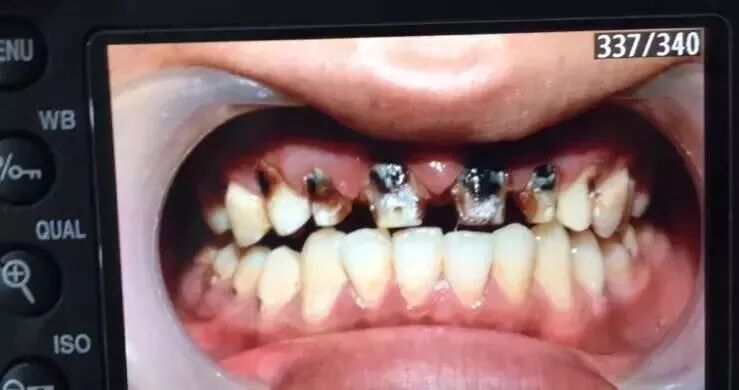

来自山西的吴医生分享了他保留的几张可乐牙病例照,我们一块来“欣赏”一下。

无独有偶,今年,就有媒体报道称,武汉一位19岁的女孩因为长期喝碳酸饮料而导致牙齿溶化,这是怎么回事?

长时间过量饮用碳酸饮料会导致牙齿酸蚀及龋坏,也就是我们常说的“可乐牙”。

被碳酸腐蚀的牙齿

“可乐牙”的初期只是牙齿怕冷、怕酸等症状,如果发展下去,前牙的结构可能逐渐变薄甚至折断;或者牙齿表面变得脆弱、碎落,继而出现牙体缺损,牙龈暴露。